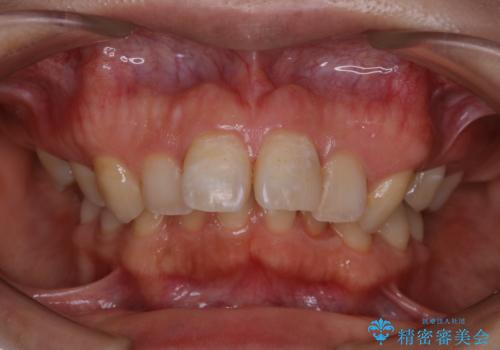

- インビザライン矯正治療の開始前にキレイな状態にしたいとのことでした。PMTC30分コースを行ってからインビザラインの型どりを行いました。

インビザラインの型どり・スキャニング(光学3Dスキャナー「iTero Element」)の前に、プラークや歯石・ステインを除去することで、ご自身本来の歯の状態となるため、綺麗なスキャニングが行えます。より精度のよいマウスピースを作成するために、PMTCを行うことをおすすめしています。